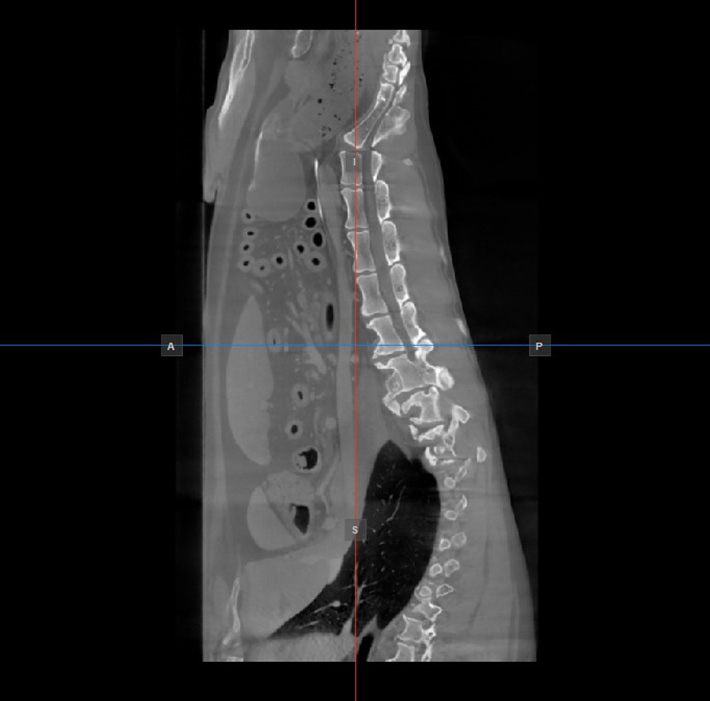

Image Orientation and Image Planes¶

The position and intersection of the other two image planes not represented in the active viewport is indicated by two vertical and horizontal lines called slicers. The endpoints of each slicer are labeled with a letter that corresponds to the appropriate direction/side of the 3D volume, based on the RAS coordinate system.

Only four sides of the available six are indicated on each 2D viewport. The labels and the corresponding side are the following:

Patient Right (R), indicating the right side of the body

Patient Left (L), indicating the left side of the body

Anterior (A), indicating the front side of the body

Posterior (P), indicating the back side of the body

Superior (S), indicating the top side of the body

Inferior (I), indicating the bottom side of the body